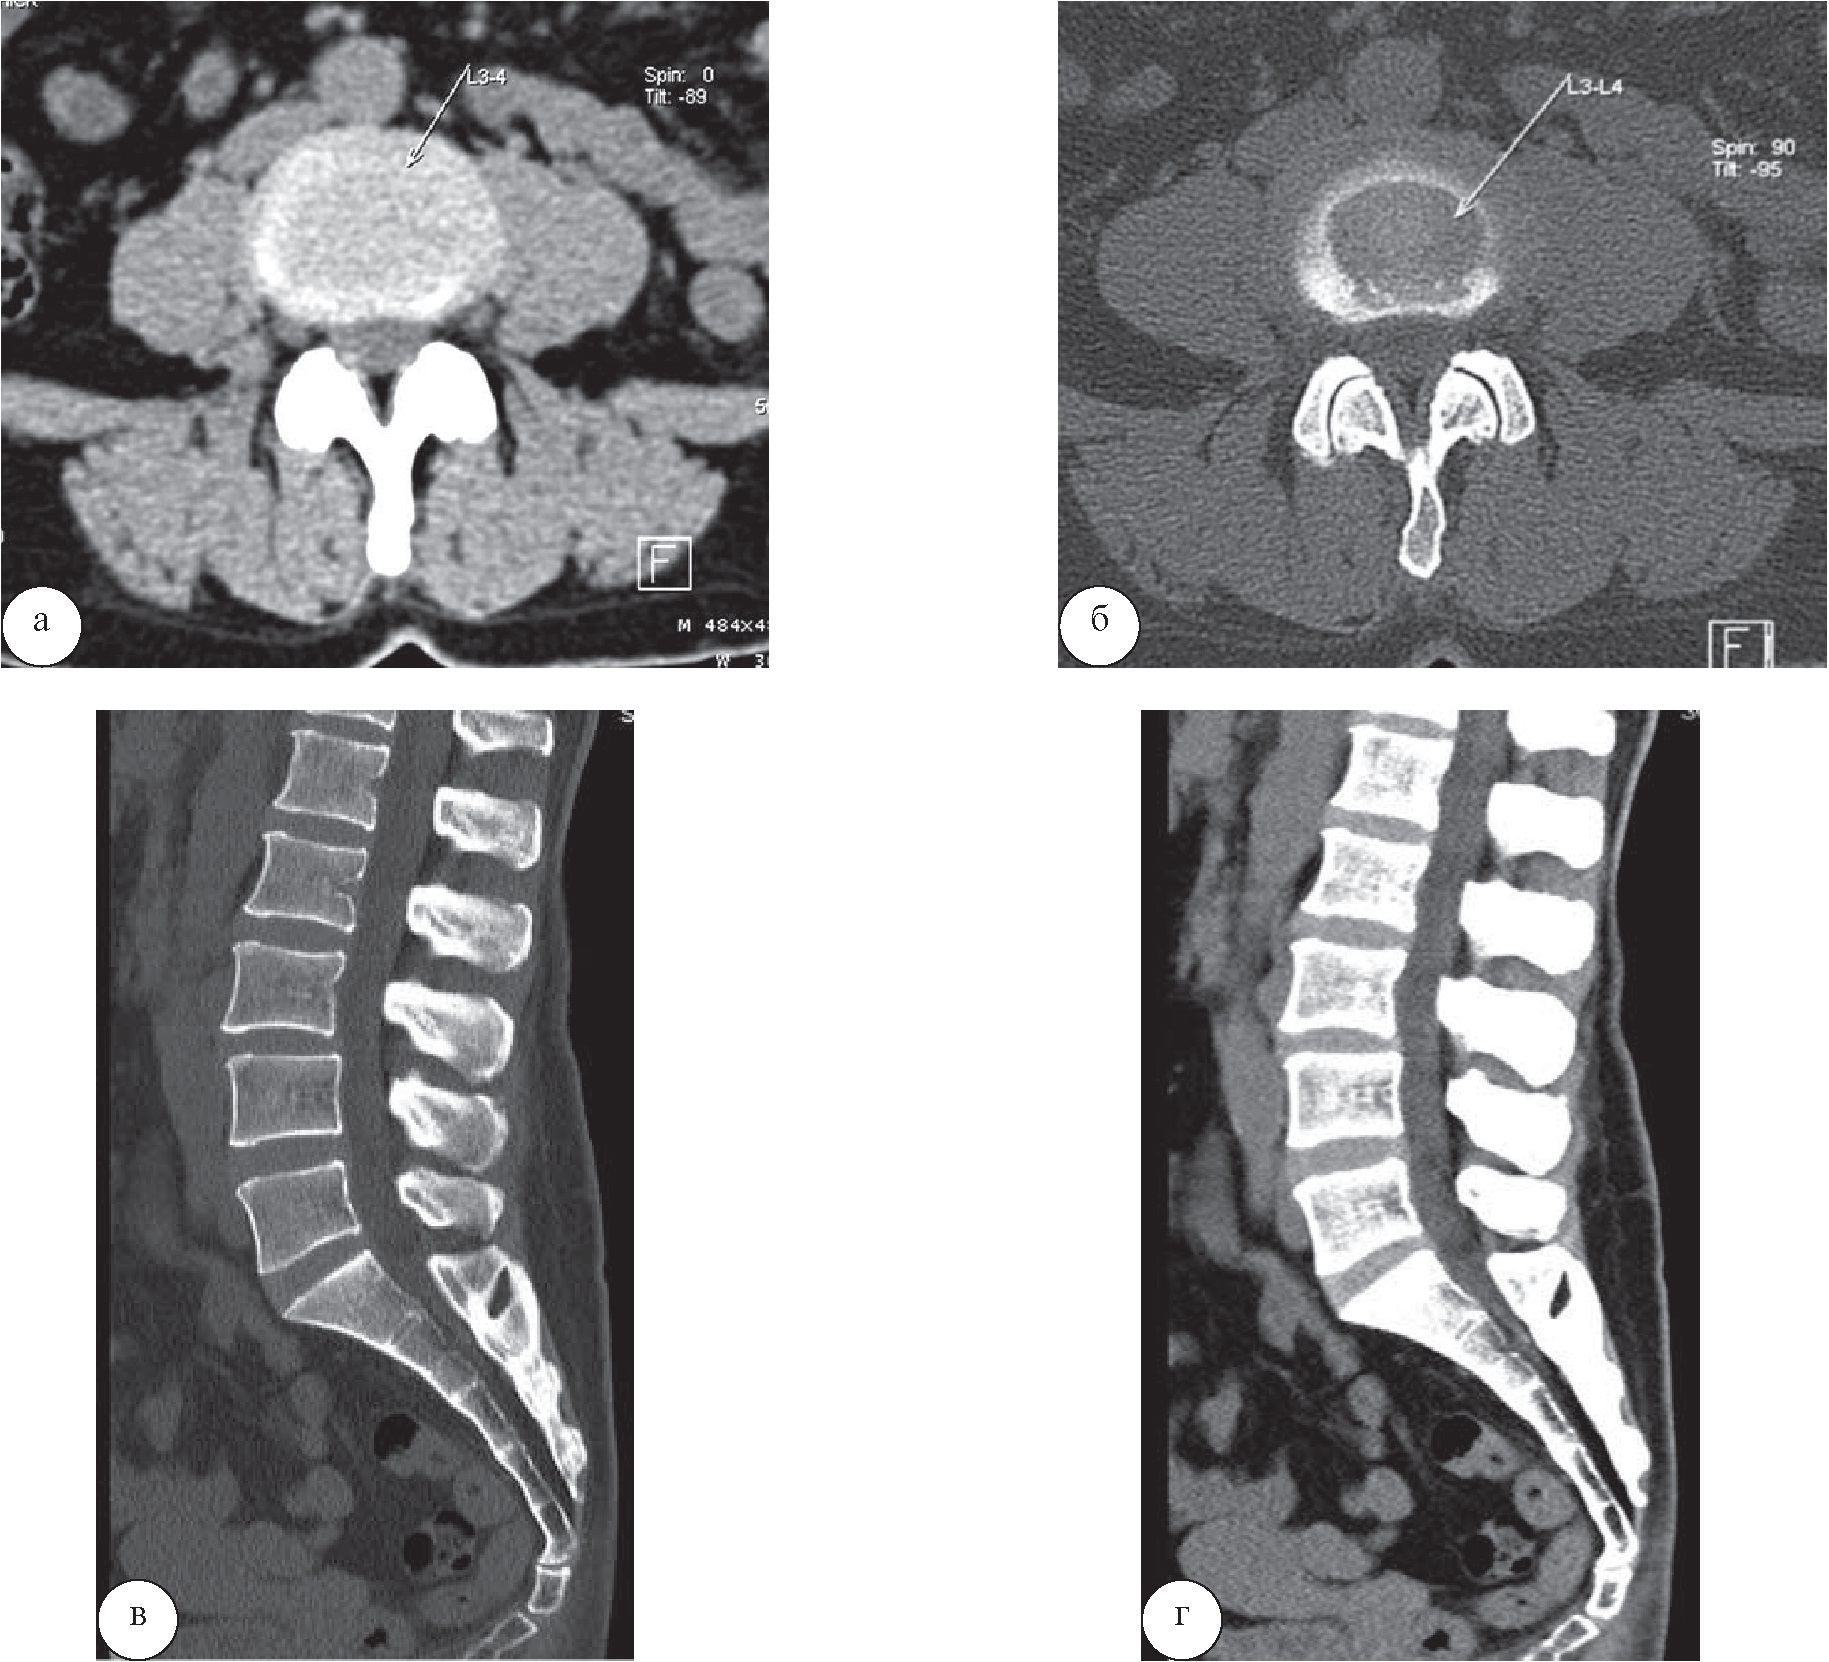

У пациентки 44 лет, прибывшей на лечение по поводу остеохондроза, в санатории выполнена КТ, позволившая диагностировать спондилолистез I степени и протрузий размерами менее 3 мм (рис. 1). В санаторной карте пациентки имелись лишь общие сведения. Данные рентгенологического обследования свидетельствовали о наличии остеохондроза, при этом спондилолистез диагностирован не был. КТ была выполнена с целью оценки изменений межпозвоночных дисков. Однако выявленные изменения не препятствовали возможности установления интенсивного режима функциональных нагрузок; противопоказаний, препятствующих назначению каких-либо методик лечебного воздействия, также не выявлено.

Рис. 1. Пациентка Т., 44 года. На КТ поясничного отдела позвоночника в аксиальной (а, б) и сагиттальной плоскостях (в, г) определяются остеохондроз поясничного отдела позвоночника I степени, протрузии межпозвонковых дисков L4–5 и L5–S1, не превышающие 3 мм, спондилоартроз, передний дегенеративный спондилолистез позвонка L3 I степени (менее 1/4 ширины позвонка) без признаков дегенеративного сужения позвоночного канала и выраженной нестабильности